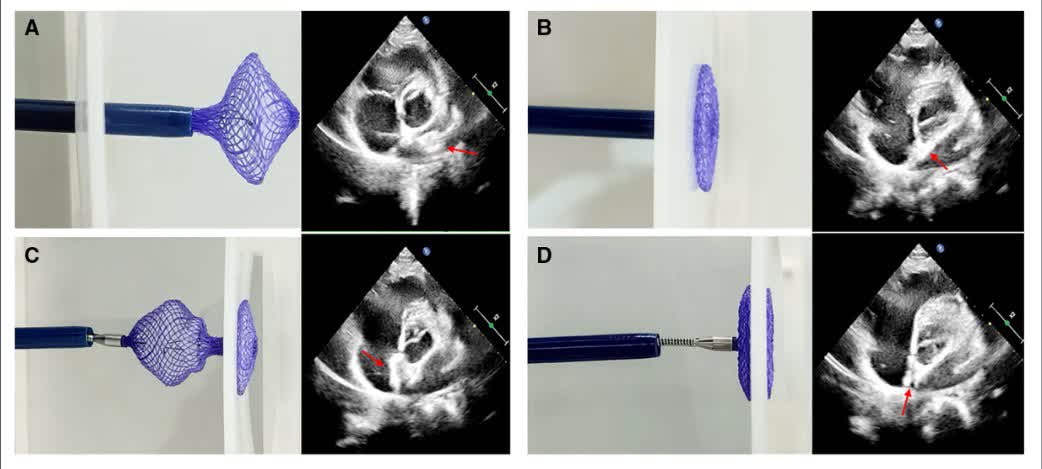

Presented today at #TCT2025 with simultaneous publication in @JACCJournals #JACCCI The first report of a βDouble LAMPOONβ procedure to mitigate the risk of LVOT obstruction after TMVR inside a βrotatedβ surgical valve, with a surgical valve post in the center of the LVOT, making